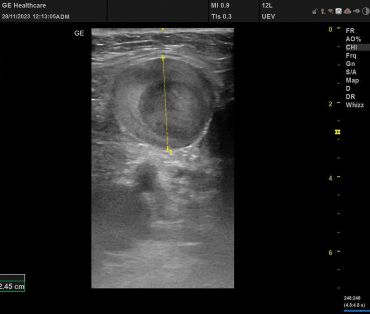

Obr. 2 Lumen VSM na levé dolní končetině před plánovaným zákrokemPři druhé návštěvě nám sdělila, že operaci na varikozitách nepodstoupila, defekty byly ošetřovány cestou dermatologického pracoviště péče o chronické rány. U pacientky byla nastavena i celková ATB terapie. Kompresní terapie neselhávala a v průběhu pěti let došlo k uzavření defektů na PDK a k parciální redukci defektu na LDK. V rámci našeho druhého vyšetření byla diagnostikována progrese insuficientních kmenových žil. Lumen VSM dosahovalo průměru více než 2 cm (obr. 2).